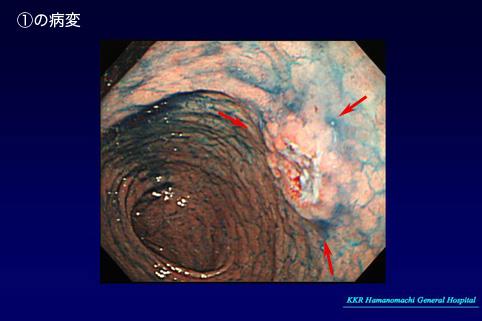

clasificación del pacienteTumor Epitelial Maligno/Otros

parte(separada por órganos)estómago(región)/antro

método de exámenEndoscopia

clasificación ectoscópica de tumoresTipo 0(tipo superficial)/Tipo IIa(IIa+IIc)

diámetro mayor del tumor15 - 19

grado de penetraciónsm

múltiples tumores(en un mismo órgano)presente(simultáneo)